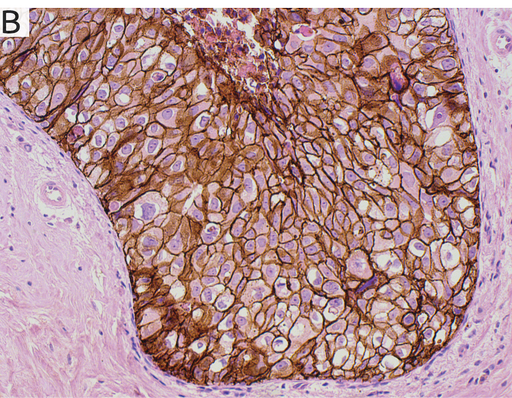

Figur 1. Jämförelse mellan Lumitos UCNP-infärgning och standard immunohistokemisk DAB-infärgning.

I bild A är bröstvävnad infärgad med Her2-UCNP–reagens för att visualisera celler med förekomst av Her2, en vanlig markör vid diagnos av bröstcancer.

Bild B visar infärgning i samma vävnadsprov som i bild A, men med standard DAB-infärgning. Både bild A och bild B visar jämförbar detaljeringsnivå men både bakgrundssignal och autofluorescens är eliminerade i Lumitos UCNP-baserade infärgning. Eliminering av all oväsentlig information från bakgrundssignal och autofluorescens ger väsentligt bättre förutsättningar för automatiserad analys baserat på t ex AI-algoritmer.